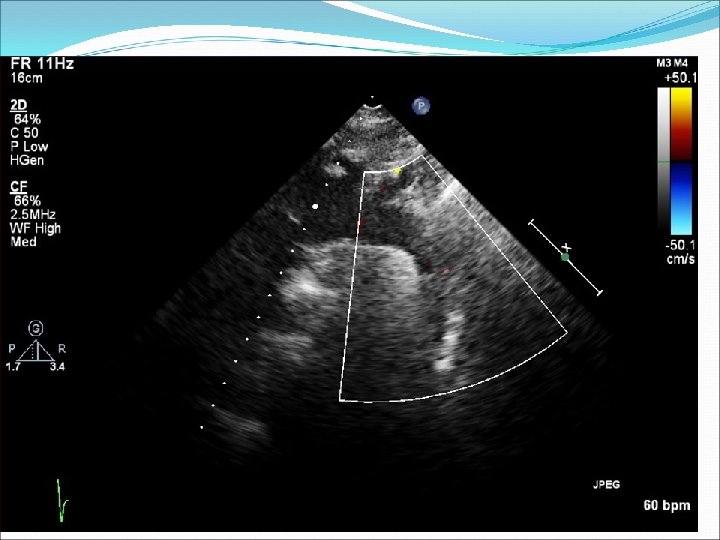

Ebsteinova anomálie �Vzácná vrozená vada � Abnormálně vyvinutá trikuspidální chlopeň je posunutá apikálně do pravé komory, septální a zadní cíp chlopně v různém rozsahu adheruje k endokardu pravé komory. K uzavírání chlopně tedy dochází hlouběji v pravé komoře, je obvyklá trikuspidální regurgitace. Vada bývá různě vyjádřená, od nevelkého posunu zóny koaptace cípů do dutiny pravé komory až po nálezy obrovské pravé síně, kterou tvoří i část původní, nyní atrializované pravé komory, samotná pravá komora je jen velmi malá. �Vada bývá spojena často s defektem septa síní nebo perzistujícím foramen ovale patens. Původně je přítomen levopravý zkrat, který se při těžké trikuspidální regurgitaci a selhávání pravé komory obrací na pravolevý. Pro vadu je typická přítomnost akcesorních atrioventrikulárních spojek převodního systému. Při vzniku supraventrikulární arytmie se těmito spojkami impulzy převádějí ze síně na komory a dochází ke vzniku maligní komorové arytmie.